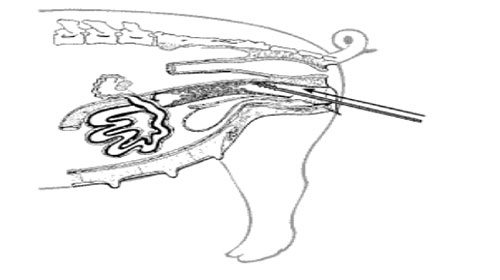

b) Introducir el catéter en la vulva con un ángulo de 45 grados hacia arriba, empújelo suavemente hasta sentir resistencia al llegar al cérvix, jale el catéter hasta asegurarse que este se ha fijado en el cérvix.

c) Conectar el tubo del semen al catéter, realizar leve presión al tubo del semen, generalmente el semen ingresa sin necesidad de llevar a cabo ninguna presión.

d) Cuando el semen no descienda, girar levemente el catéter, buscando acomodarlo mejor.

e) Cuando el tubo que contiene el semen, no tiene aire en su interior, debe desconectarse y conectarlo de nuevo para permitir que le ingrese nuevamente aire para que el semen fluya hasta introducir la totalidad del semen.

f) Una vez introducido la totalidad del semen, girar el catéter hacia la derecha para desconectarlo del cérvix y retirarlo.